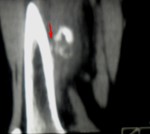

По вот этому срезу у меня складывается впечатление, что этот участок связан с костью - экхондрома? параоссальная хондрома? образование мягких тканей (фиброма)? Мне кажетс, что для того, чтобы обызвествилась гематома травма должна быть давненько, поэтому для меня обызвествленная гематома под большим вопросом.

2.Если это обызествленная гематома то. к чему реакция периоста, да еще и ТАКАЯ. да и мягкотканный компонент присутствует вокруг.